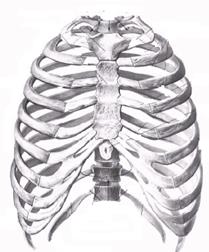

ФІЗІОЛОГІЯ ДИХАЛЬНОЇ СИСТЕМИ

Дихання – це фізіологічний процес направлений на забезпечення окисно – відновних процесів в організмі людини.

Етапи дихання

Ø зовнішнє дихання \ вентиляція легень\

Ø обмін газів в легенях \ між альвеолярним повітрям і кров’ю капілярів малого кола кровообігу \

Ø транспорт газів кров’ю

Ø обмін газів в тканинах між кровю капілярів великого кола кровообігу і тканинами

Ø внутрішнє дихання – вивчає біохімія.

Показники зовнішнього дихання

Частота дихання

Глибина дихання

Екскурсія грудної клітки

ЖЄЛ

Легенева вентиляція

Показники спірометрії

Ø Дихальний об’єм – це кількість повітря яке людина вдихає і видихає в спокої –

300 – 700 мл;

Ø Резервний об’єм вдиху – це кількість повітря яке можна ввести в легені, якщо вслід за

1500 – 2000 мл4

спокійним вдихом зробити максимально можливий.

Ø Резервний об’єм видиху – це кількість повітря яке можна вивести в легені, якщо вслід за

1500 – 2000 мл спокійним видихом зробити максимально можливий.

Залишковий об’єм – це об’єм, який залишається в легенях після максимального видиху.

1000 - 1500 мл.

РЕГУЛЯЦІЯ РОБОТИ ДИХАЛЬНОГО ЦЕНТРА

Регуляція роботи дихального центра здійснюється за рахунок

Ø гуморального впливу;

Ø рефлекторного впливу;

Ø імпульсів з відділів головного мозку.

1.Гуморальний вплив

Специфічним регулятором активності дихального центра являється СО2,

Хеморецептори ретикулярної формації, судинної системи \ каротидний синус, дуга аорти\

Збудження від хеморецепторів поступає до інспіратор них ядер дихального центру - вдих

2. Рефлекторні впливи

Ø постійні рефлекси – при подразненні рецепторів альвеол, легень, плеври, пропріорецепторів дихальних мязів. Найважливіший рефлекс на роз тяжіння альвеол.

Ø Непостійні рефлекси – подразнення рецепторів слизової носа, верхніх дихальних шляхів, скелетних мязів, шлунка.

3. Вплив кори головного мозку.

Забезпечує свідоме керування диханням. Ми можемо затримати дихання. Дихати частіше.

Таким чином кора забезпечує пристосування дихальної системи до змін навколишнього середовища, або умов – фізичне навантаження та ін..